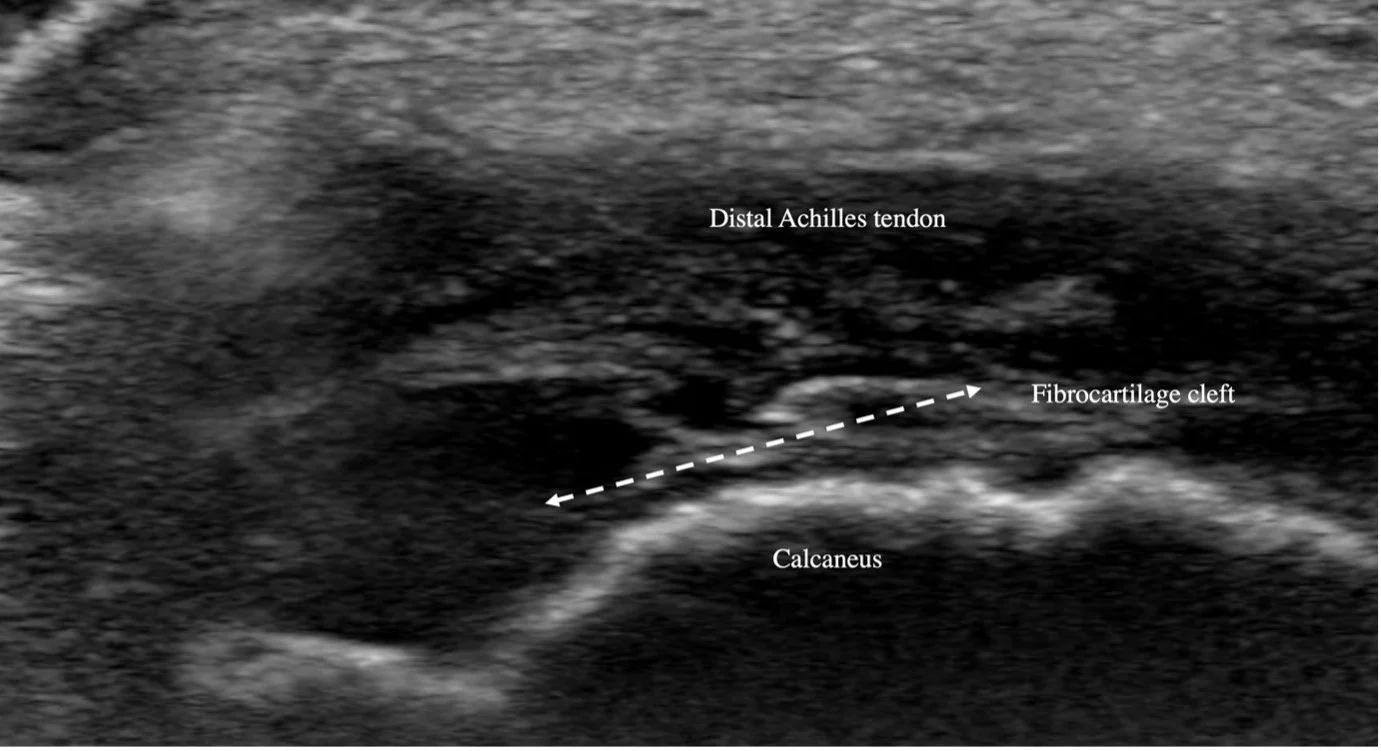

A 10-year-old boy, very active, presents with a 4-month history of heel pain, aggravated by activity. The onset coincided with a fall from his scooter. Is this Sever’s disease?

Have a look at the images and see if they match the generally accepted clinical picture of Sever’s.

Sometimes the reported onset may be a red herring. In this case, though all other history items pointed to Sever’s disease, it clearly wasn’t. When we examine children with Sever’s, there are seldom objective findings of injury, and “no cause for pain identified” ultrasound examination is reassuring. Sometimes however, we do find an injury or damage, and this usually necessitates further investigation or specific management. This case shows it’s well worth investigating clinical symptoms of Sever’s disease.